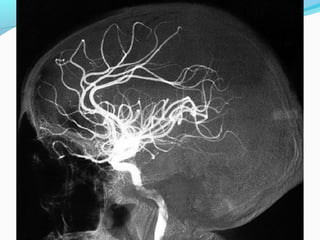

-O encéfalo é irrigado basicamente por dois sistemas:

- carotídeo

- vertebral

- Essas artéria formam o Polígono de Willis de onde partem as principais

artérias para a vascularização cerebral.

- Penetra na cavidade craniana pelo canal carotídeo do osso

temporal

- Atravessa o Seio Cavernoso e forma o Sifão Carotídeo

-Divide-se nos ramos terminais:

- artérias cerebrais média

- acompanha o sulco lateral

- artérias cerebrais anterior

- acompanha o sulco acima do corpo caloso

-O encéfalo éirrigado basicamente por dois sistemas: - carotídeo - vertebral - Essas artéria formam o Polígono de Willis de onde partem as principais artérias para a vascularização cerebral. -- Artérias finas como veias propensas a hemorragias - Túnica média com menos fibras musculares - Túnica elástica interna mais espessa e tortuosa: amortece a pulsação arterial.

- Penetra nacavidade craniana pelo canal carotídeo do osso temporal - Atravessa o Seio Cavernoso e forma o Sifão Carotídeo -Divide-se nos ramos terminais: - artérias cerebrais média - acompanha o sulco lateral - artérias cerebrais anterior - acompanha o sulco acima do corpo caloso